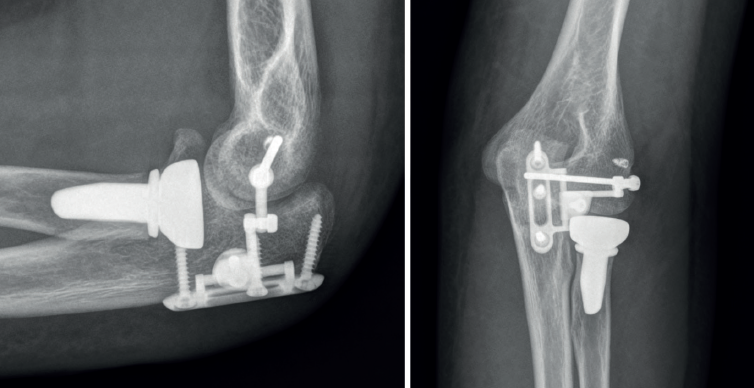

Como alternativa a esta técnica, Orbay describió por primera vez en 2014 el IJS®. Este dispositivo está diseñado como estabilizador adicional cuando exista suficiente stock óseo e inestabilidad residual tras el tratamiento quirúrgico de las estructuras lesionadas. Todavía no existen indicaciones claras y en muchas ocasiones recae en la experiencia del cirujano la decisión de usarlo(22). En la bibliografía actualmente publicada, su uso más común es en el tratamiento de la inestabilidad residual tras una tríada terrible de codo(23,24,25).

En cuanto a la técnica quirúrgica, la necesidad de usar un dispositivo adicional como el IJS® para aportar estabilidad debería valorarse en la planificación preoperatoria. Se debe tener en cuenta para dejar libre el centro de rotación del epicóndilo lateral, donde se colocará el pin del axis, y no reinsertar en ese mismo punto el LCL®, ya que, como se ha comentado, modificarlo aumenta de forma notable las fuerzas a las que se somete la articulación.

Para reparar el LCL, este puede reinsertarse con un arpón que normalmente se sitúa posterior y proximal al punto elegido para el pin(24,25).

Para facilitar este paso, muchos cirujanos proceden en primer lugar a la colocación del pin humeral (axis pin) o una aguja de Kirschner a nivel del punto isométrico antes de realizar la reparación osteoligamentosa(22). En este paso se comprueba la correcta colocación del pin con una guía y mediante fluoroscopia. Es importante, para evitar lesionar el nervio cubital, no traspasar la cortical medial y, si la medida queda entre 2 longitudes, elegir la más corta (Figura 6).

Tras realizar este paso, se realiza la reparación del resto de las estructuras. Al concluirla, se verifica la estabilidad y la congruencia articular a lo largo de todo el arco de movilidad en flexoextensión y, si se evidencia inestabilidad franca, se procede a la colocación del dispositivo según está descrita la técnica por el fabricante (Figura 7).